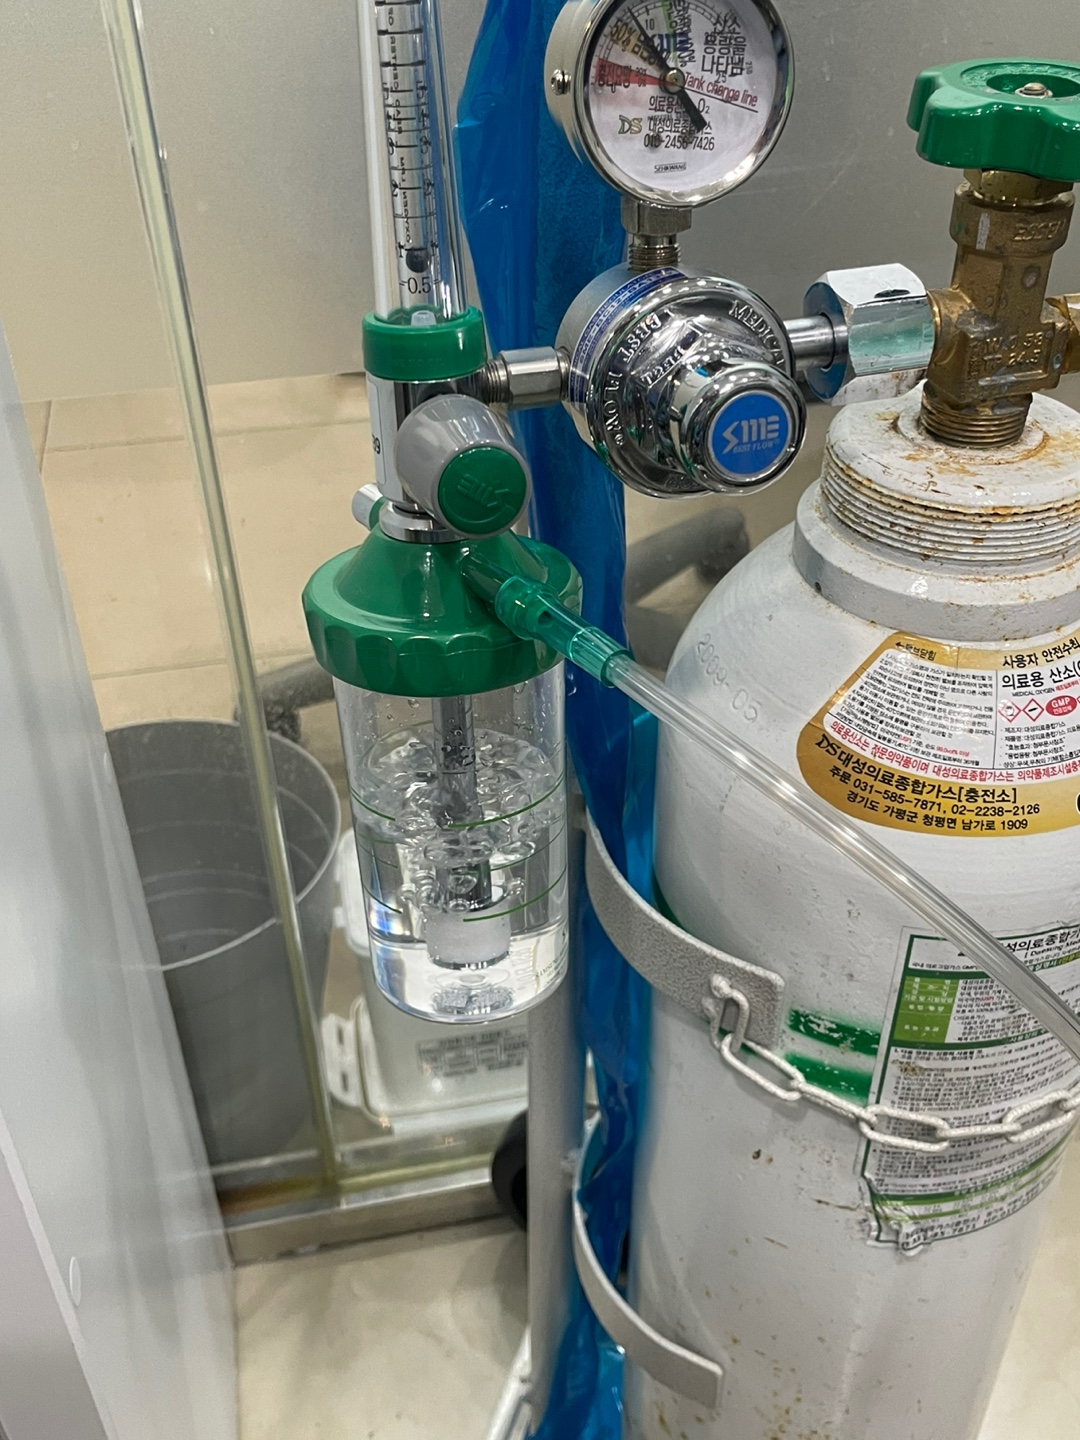

첫째 안전한 수술

두번째는 최소의 수술 시간 이었습니다.

안전한 수술을 위하여 처음부터 산소를 코에 착용해서 산소포화도를 95프로 이상 계속 유지 했습니다. 역전제인 플루마제닐은 당연히 준비 되어 있었습니다.